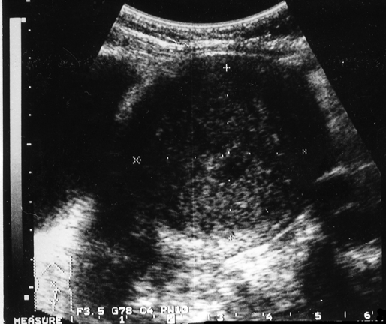

Клинико-морфологические и ультразвуковые параллели позволяют клиницисту на дооперационном периоде составить представление о степени распространения опухолевого процесса, наличия метастазов не только в зонах регионарного метастазирования, но и в органах брюшной полости (рис. 1–4).

Рисунок 2. Прорастание рака эндометрия всех оболочек матки

Сравнительное изучение результатов морфологического исследования удаленной матки с ультразвуковыми находками показало число совпадений при микроскопической инвазии опухолью миометрия в 66,6% случаев. Следует отметить, что точность совпадений приближается к 100% при глубине инвазии опухолью мышечной оболочки матки более 1 см.

Совпадение морфологических и сонографических данных о размерах первичной опухоли в матке и ее локализации отмечено соответственно в 86 и 45,7% наблюдений. Значительна частота совпадений и при большом поражении полости матки. Так, у 52,4% пациенток с тотальным поражением полости матки и у 88,2% пациенток с локализацией опухоли в полости матки с переходом на цервикальный канал данные УЗТ и гистологического заключения совпали. Этот показатель снижается до 15,8% при локализации аденокарциномы в области дна матки и ее трубных углов.